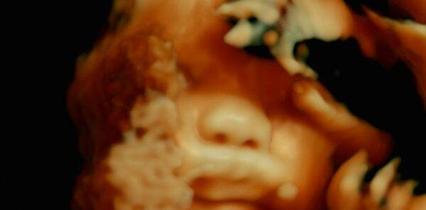

Catherine Liu s’attache ainsi à montrer que derrière les principes moraux défendus par les CPIS se cachent en réalité des intérêts de classe : « …les CPIS surent se distinguer de ceux qui leur étaient économiquement inférieurs de façon moralement justifiable. » Les CPIS investissent en effet certains domaines, comme la parentalité, l’éducation, la culture ou encore la sexualité, pour mieux afficher leur supériorité vis-à-vis des classes populaires : « Lire des livres, élever des enfants, se nourrir, rester en bonne santé ou faire l’amour ont constitué autant d’occasions de démontrer qu’on faisait partie des individus les plus évolués de l’histoire humaine, tant sur le plan affectif que culturel. » Certains de ces domaines, notamment la puériculture et l’éducation, correspondent d’ailleurs à des sphères où l’influence de l’Etat s’est progressivement délitée au profit d’institutions privées et des catégories les plus favorisées de la société : « Nul besoin d’être socialiste pour constater que la puériculture, la santé et l’éducation constituent les domaines où les privilèges de classe sont reproduits de la manière la plus extrême et la plus spectaculaire ». Catherine Liu évoque notamment longuement le cas des universités, qui sont devenues des terrains de luttes sociétales, alors que la recherche publique et l’autonomie des chercheurs s’affaiblissent progressivement. La classe managériale fait par exemple front contre les violences sexuelles à l’université mais ne lutte jamais contre l’insécurité professionnelle et les inégalités économiques qui sont souvent à l’origine de ces violences : « En matière de sexe, il ne peut exister aucun plaisir ni aucune liberté tant que nous ne serons pas affranchis de l’angoisse économique que représente la survie au quotidien… ».